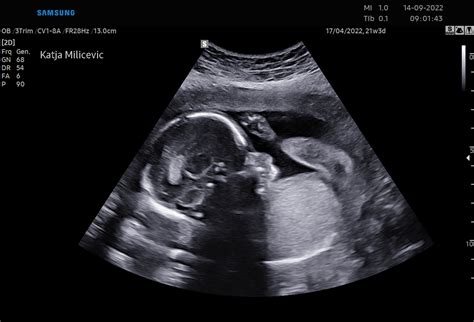

V 24. tednu nosečnosti plod že meri približno 30 cm v dolžino in tehta okrog 540 gramov. V tem obdobju je otrok že sposoben samostojnega preživetja zunaj maternice, čeprav bi potreboval intenzivno neonatalno nego. Stopnja preživetja nedonošenčkov, rojenih v 24. tednu, je okoli 42-59 %. V pljučih ploda se prične proizvajanje sluzi, tako imenovanega surfaktanta, ki omogoča, da se zračni mehurčki napolnijo z zrakom, ne da bi se zlepili. To je ključen korak za pripravo na samostojno dihanje po rojstvu.

Oči ploda že reagirajo na svetlobo, kar pomeni, da lahko zazna svetlobo, ki prodira skozi materino telo. Nozdrvi se odpirajo, kar je del priprave na dihanje. Refleksi postajajo vse bolj izraziti, kar nakazuje na nadaljnji razvoj živčevja. V telesu ploda se proizvajajo bele krvne celice, ki so ključne za imunski sistem. Možgani se intenzivno razvijajo, kar bo omogočilo kompleksnejše funkcije v prihodnosti. Plod lahko že razlikuje zvoke, zato lahko reagira na glasbo in že lahko prepozna mamin glas.